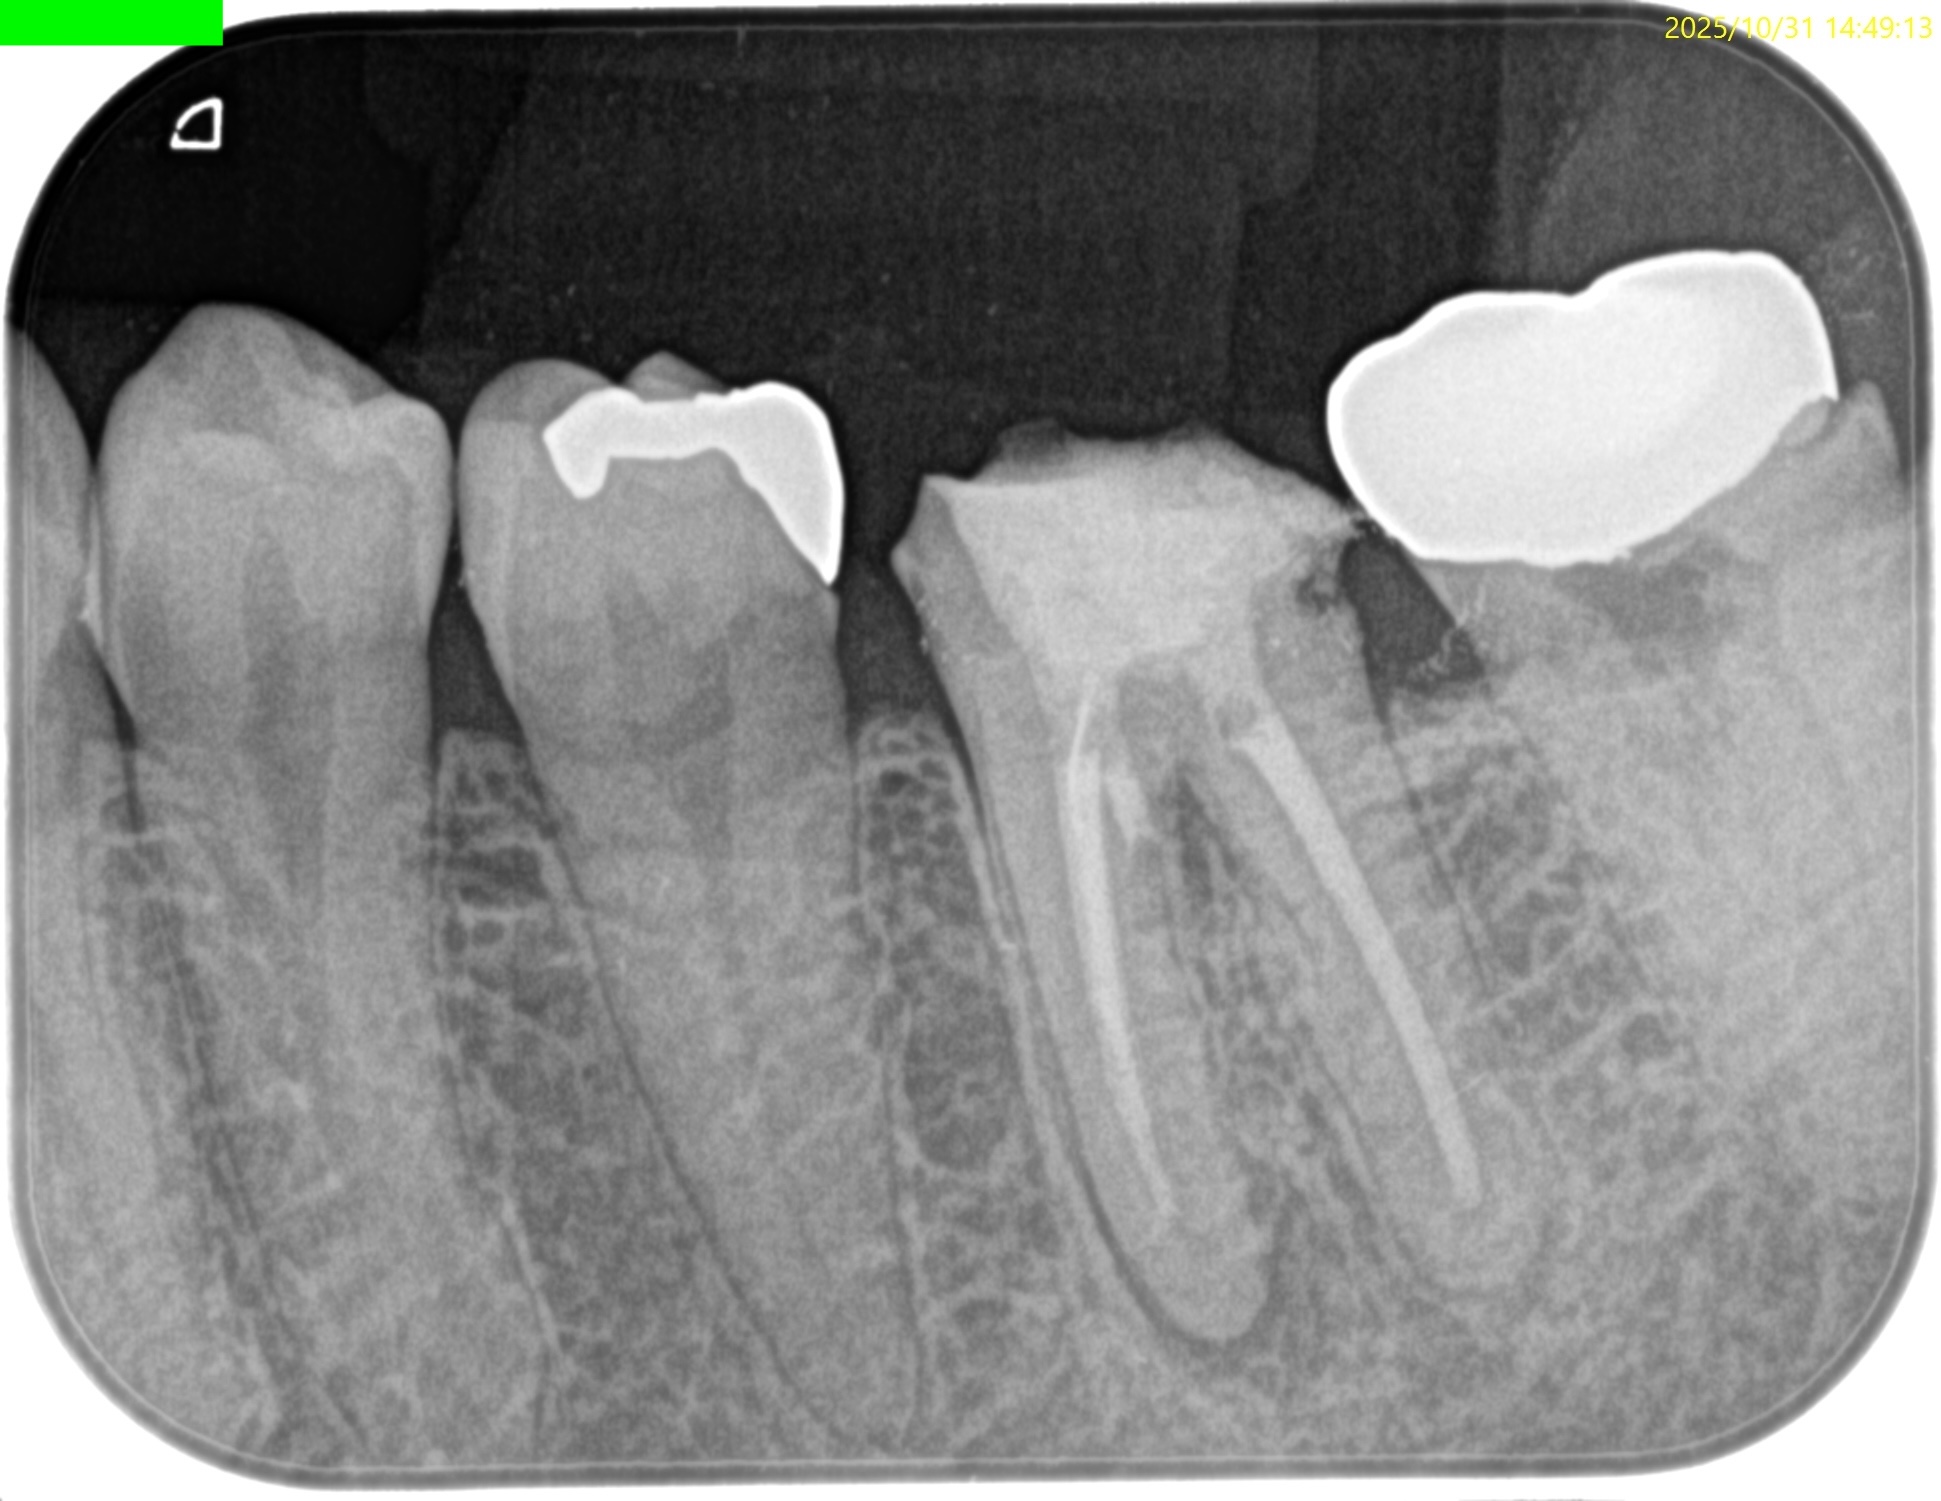

#18 RCT(2025.12.4)

除冠し当該部位を削ると…

既に虫歯が縁下にまで及んでいた。

これが主訴(左下奥がうずいたり、歯磨きをするときに痛い…食事をするときにも痛い。痛みが強くなると顎まで痛みが出ることがある…)の原因だったのだろう。

ではそれになぜ気付けたか?だが、

明らかにCBCTの存在がなければこの存在に気づけなかっただろう。